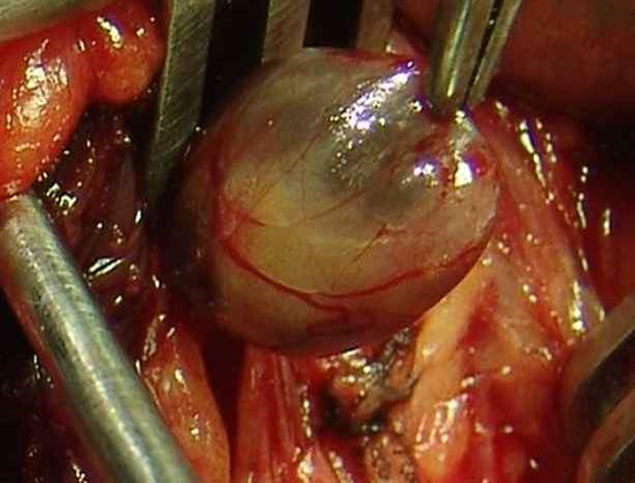

Surgical Management

- If adenoma is present:

- Surgical removal of the adenoma

Surgery

Primary hyperparathyroidism: is usually due to a parathyroid benign adenoma (75%) or parathyroid hyperplasia (20%). 1.0% have parathyroid carcinoma.

- Urgent parathyroidectomy.